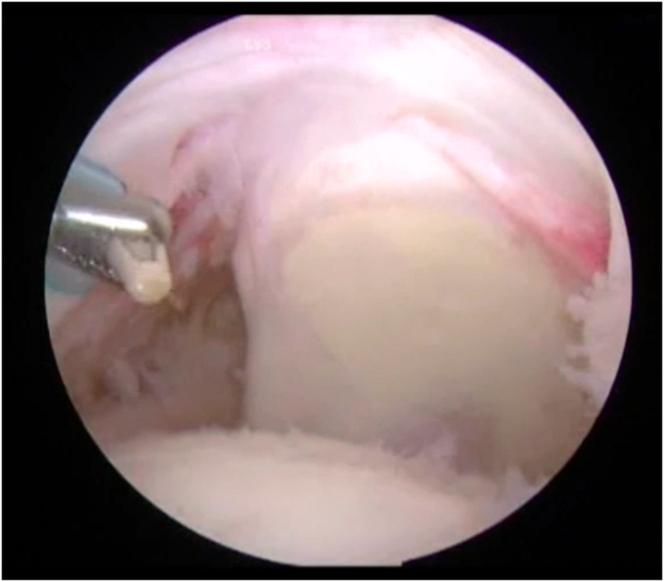

关节镜下取出突出及松动的肩关节内固定物的技术与技巧

Techniques and Tips to Arthroscopically Remove Prominent and Loose Shoulder Joint Hardware.

The number of arthroscopic shoulder operations has continued to steadily increase in recent years, with a projection of over 500,000 rotator cuff operations in 2023. Although the incidence of anchor pullout, hardware failure, and aberrant hardware placement is relatively low, this increased volume of shoulder operations has inevitably resulted in a consequent increase in the number of patients who experience such hardware complications. These hardware issues can cause significant pain, limit shoulder function, and cause permanent damage to the shoulder articular cartilage. The described arthroscopic techniques are presented to provide tools and strategies to safely and effectively remove prominent and loose shoulder joint hardware.

近年来,肩关节镜手术的数量持续稳步增长,预计2023年肩袖手术将超过50万例。尽管锚钉拔出、硬件故障和硬件放置异常的发生率相对较低,但肩关节手术数量的增加不可避免地导致了此类硬件并发症患者数量的相应增加。这些硬件问题可导致严重疼痛、限制肩部功能,并对肩关节软骨造成永久性损伤。本文介绍了关节镜技术,以提供安全有效地取出突出和松动的肩关节硬件的工具和策略。